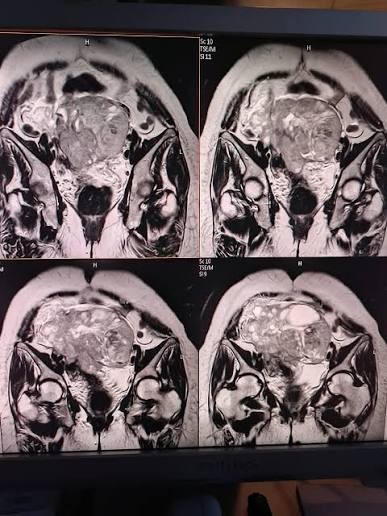

قالت وزارة الصحة في غزة إنها تمكنت استعادة خدمات التصوير الطبي التشخيصية بتفعيل التصوير الطبي الملون في مركز صحي الدرج بمدينة غزة.

وبين مدير وحدة التصوير الطبي إبراهيم عباس، بدء إجراء الفحوصات بالتصوير الملون لعدد من الحالات.

وذكر أن الخدمة ساهمت بشكل كبير في التشخيص ومتابعة العلاج اللازم.